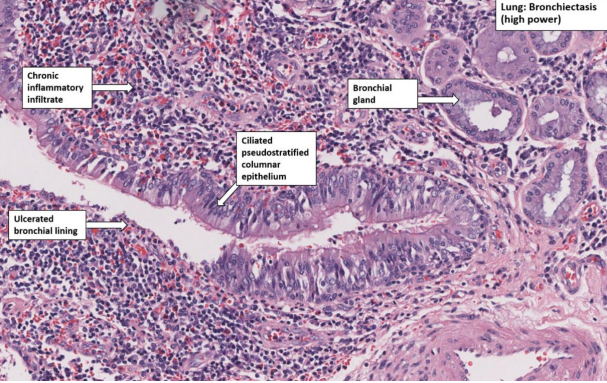

Bronchiectasis

A

Irreversible dilation of bronchi caused by destruction of bronchial wall muscle and elastic components

Clinical symptoms:

- a productive cough, often mucopurulent sputum and haemoptysis is common as bronchial inflammation erodes through the walls of adjacent bronchial arteries

- pneumonia is a common complication, hypoxia and pulmonary hypertension

- acute reversible dilation of bronchi may occur as a consequence of bacterial or viral infection

Bronchiectasis - Microscopic

Severe inflammation of bronchi and bronchioles

Destruction of all components of the bronchial wall

Collapse of distal lung parenchyma

Mucus production

Evidence of squamous metaplasia with increased goblet cells

Lymphoid follicles often seen in bronchial walls and distal bronchi

Bronchioles are scarred and often obliterated